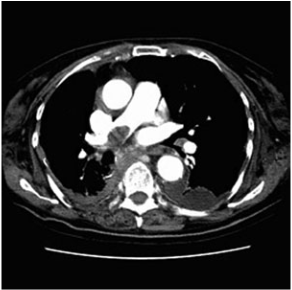

6.

Two and a half weeks after coronary artery by-

pass grafting, a 63-year-old man returns to the

emergency department acutely short of breath.

The patient states that he began having chest

pain and shortness of breath approximately 1

hour earlier. He has a history of hypertension,

diabetes, and two myocardial infarctions. On

examination he is hypoxic with an oxygen satu-

ration of 86% on room air. Other vital signs

and results of a physical examination are nor-

mal. ECG shows no interval change from his

most recent ECG. CT of the chest is shown in

the image. What is the most likely etiology of

this patient’s shortness of breath?

Recent surgery and

likely limited mobility in the postoperative pe-

riod are two risk factors for pulmonary em-

bolus. The enhanced CT scan of the chest

shows a fi lling defect within the right pulmo-

nary artery consistent with pulmonary em-

bolus. The patient should be treated with anti-

coagulation. Other common risk factors for

deep venous thrombosis and pulmonary em-

bolus include malignancy, pregnancy, and hy-

percoagulable states.